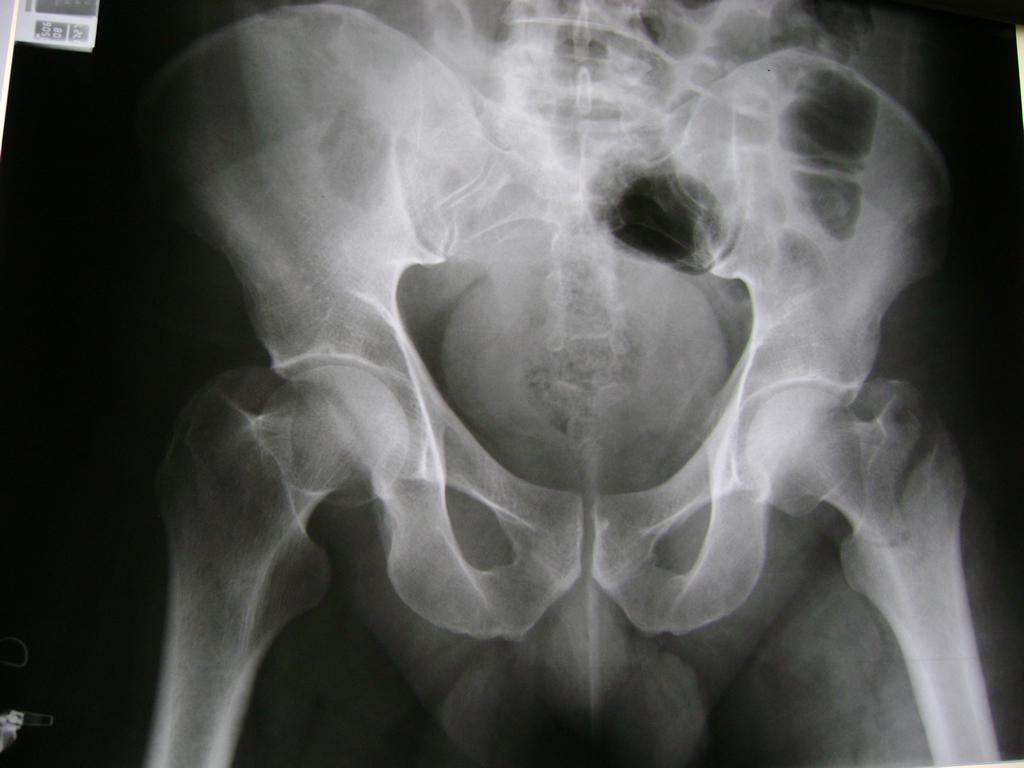

Fémur - Cadera

La cirugía de fractura de cadera se realiza para reparar una ruptura en la parte superior del hueso del muslo. Este hueso se denomina fémur.

Es parte de la articulación coxofemoral. Si una fractura de cadera no recibe tratamiento, es posible que deba permanecer en una silla o en la cama.